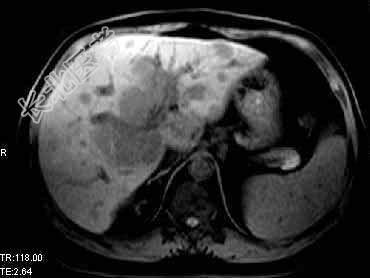

- 单项选择题根据所提供的图像,最可能的诊断是 ( )

A、肝转移癌

B、肝细胞癌

C、肝胆管细胞癌

D、肝血管瘤

E、以上都不是